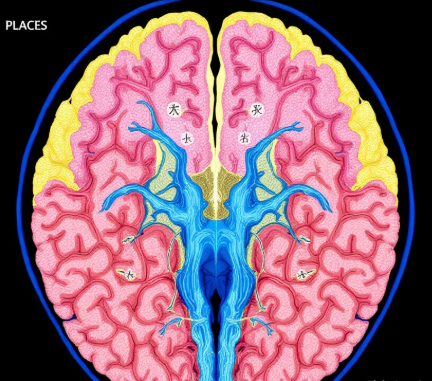

치매의 형태는 뇌에서 어떤 변화가 일어났는지에 따라 나뉩니다. 혈관성 치매와 알츠하이머는 발생 기전 자체가 다르기 때문에 치료 목표도 달라집니다.

• 혈관성 치매는 뇌혈관이 막히거나 터지면서 뇌세포가 손상되어 발생

• 알츠하이머는 베타아밀로이드 단백질이 뇌에 쌓이면서 뇌세포가 서서히 죽는 질환

• 혈관성 치매는 뇌졸중과 관련 있는 경우가 많음

• 알츠하이머는 명확한 혈관 이상 없이 서서히 기억력이 저하됨

즉, 혈관성 치매는 혈류의 문제, 알츠하이머는 신경세포의 퇴화라는 차이가 있습니다.